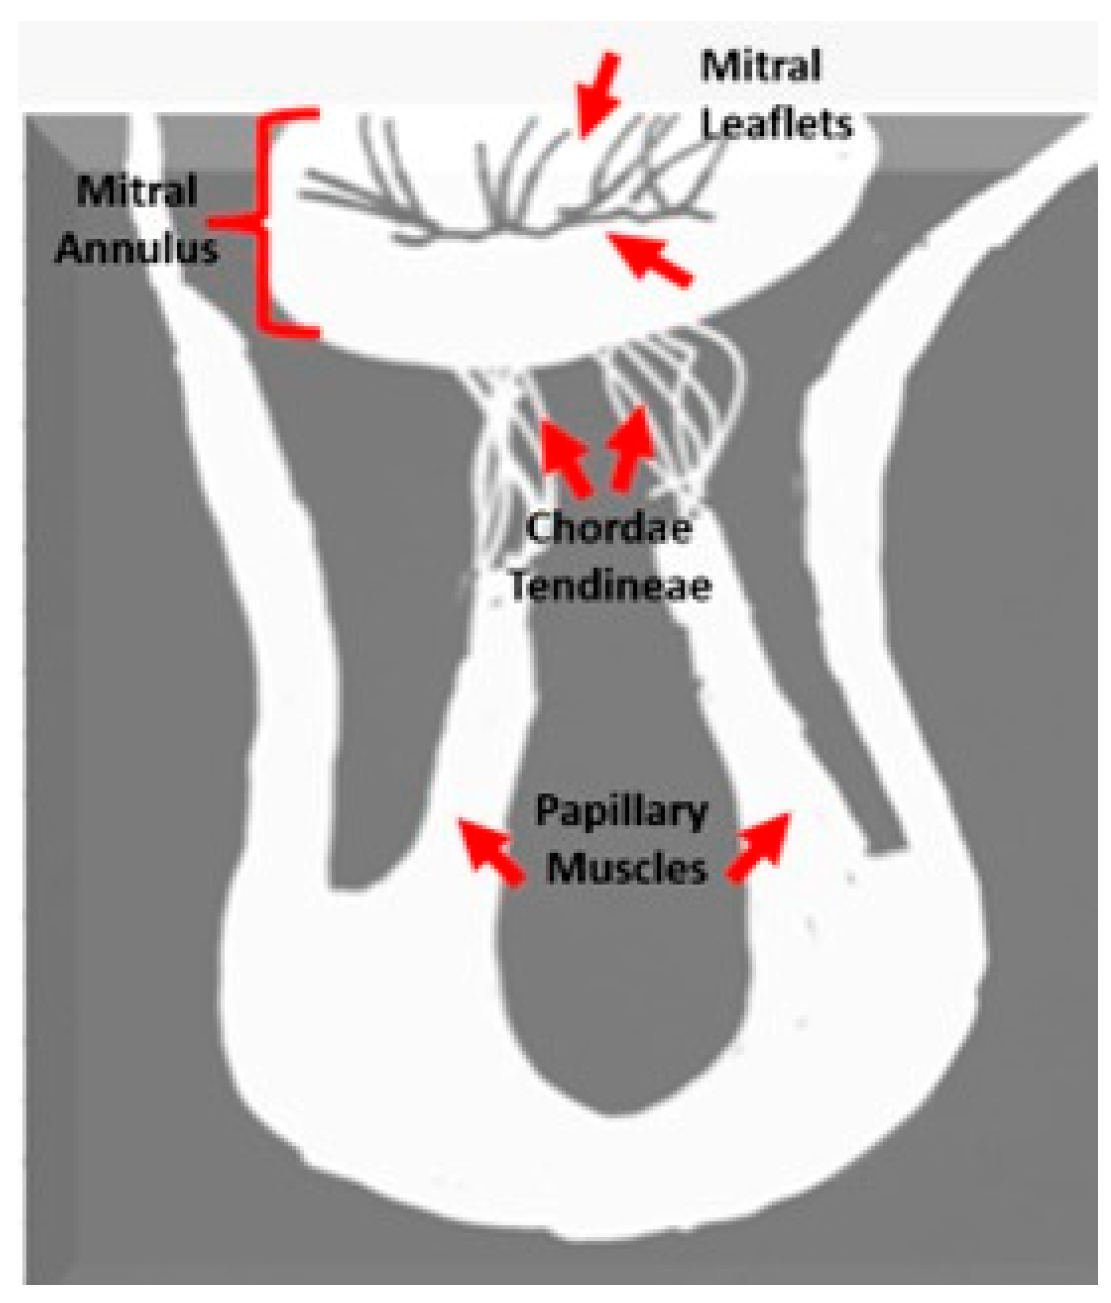

2.4. Image Analysis